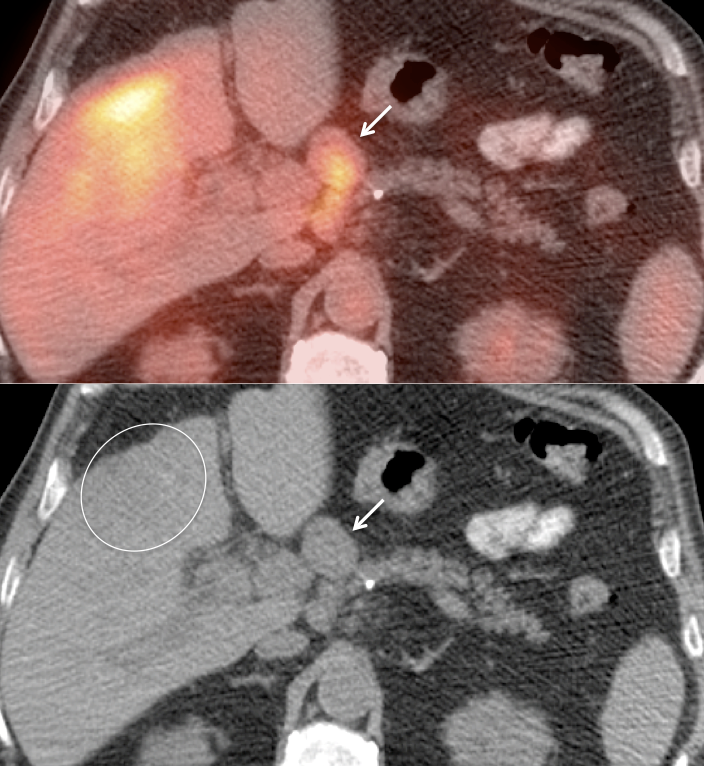

Indications for PET/CT:

Initial Staging of Gallbladder Carcinoma:

- While PET/CT can detect the primary lesion, its true utility lies in the detection of regional nodes and distant metastatic disease.

- Distant Disease: Most commonly to the liver, lung and brain.